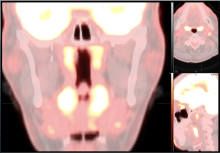

Douglas E. Holt, M.D., a radiation oncologist at Eastern Idaho Regional Medical Center, explains the use of 3-D virtual reality volumetric imaging review to help improve cancer patients’ understanding of their disease and treatment. Pictures are worth a thousand words, and moving pictures inside a patient's body even more. Holt said using virtual reality to go through the patient's anatomy in 3D and to show them what is wrong and how it will be treated offers a new level of understanding that is not possible using a discussion or a couple still images from their medical imaging.

Holt presented this study as a late-breaker at the 2021 American Society of Radiation Oncology (ASTRO) annual meeting.